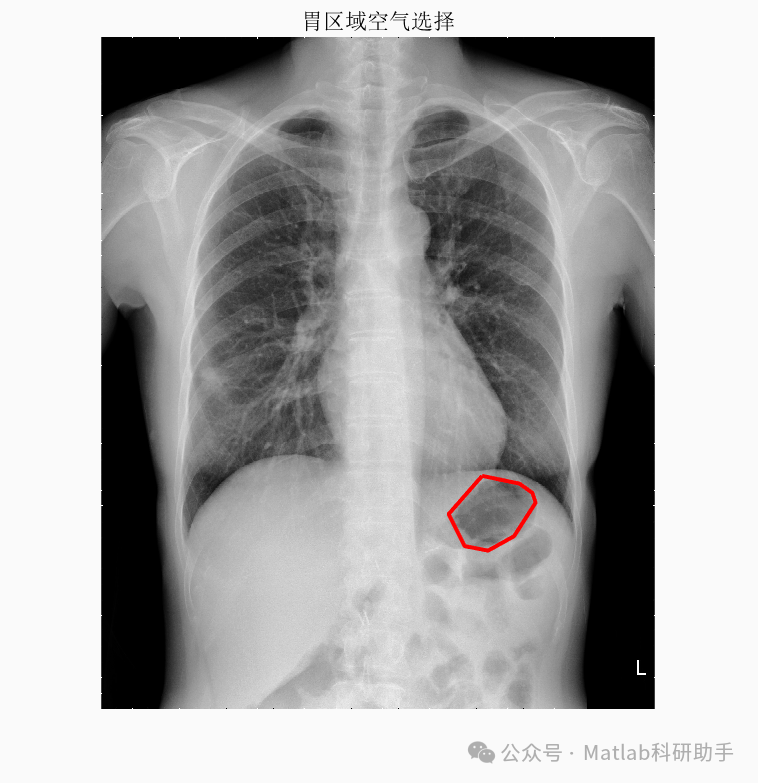

⛳️ 运行结果